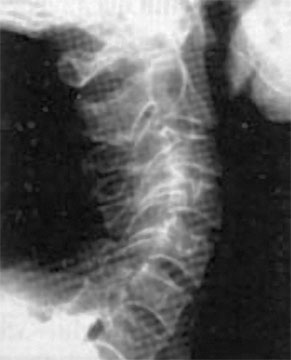

Посмотришь на лицо, вроде бы женщина еще молодая, ухаживающая за собой. А взглянешь со стороны – прямо старушка ковыляет – ссутулилась, шейка вперед подалась, плечики сжались. Хорошо, сама себя не видит, а то бы очень огорчилась. Из-за того, что с возрастом диски между позвонками уплощаются, длина шеи укорачивается и частенько весьма значительно (рис. 69).

Рис. 69. Шейный отдел позвоночника

Появление поперечных морщин и складок на боковой поверхности шеи служит точной приметой этого явления.